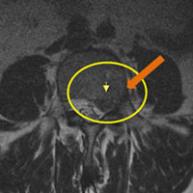

MRI

㸮 ٸ ߰

㸮 ְ , ٱ ־.